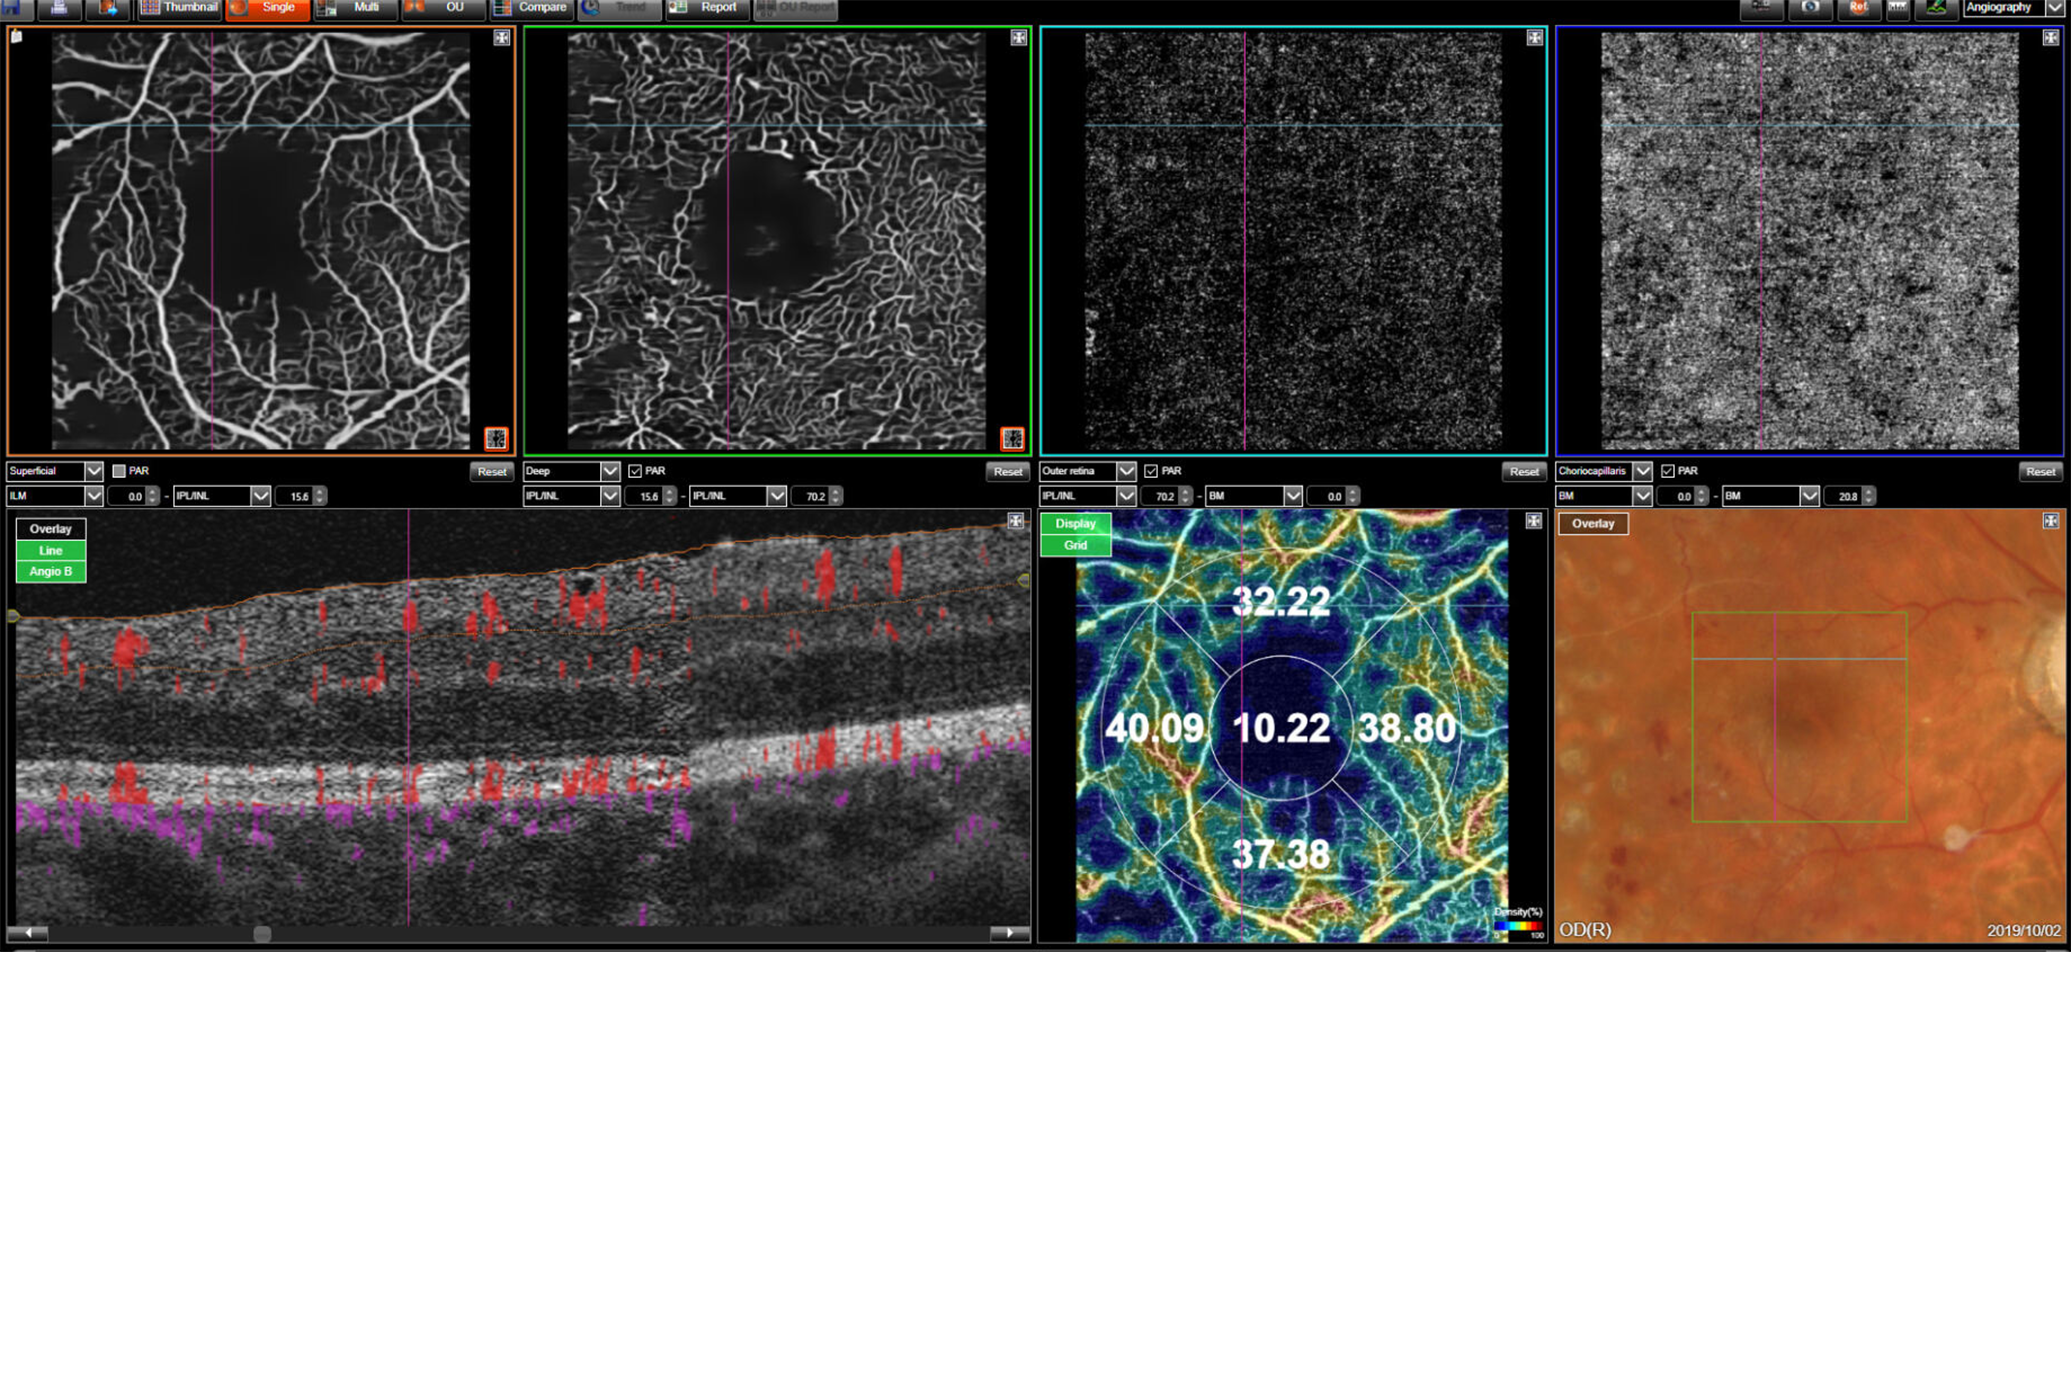

Maestro2

Introducing automated OCT, true color fundus photography, and automated OCT-A in one instrument.

With the touch of a button, OCT-A provides instantaneous vascular structure information – from our world-renowned, multi-modal OCT solution.

OCT-A data can be quantified with OCT-A density maps and associated metrics.

Courtesy: Dr. Patrick SPORTIELLO, MD,FEBO, Ophthalmology Practice, Issoire, France